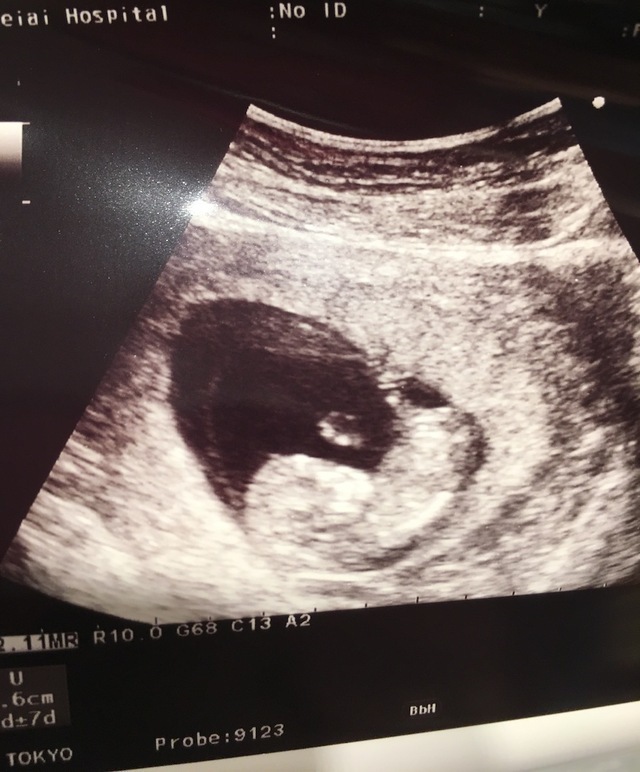

11週6日(11w6d・性別不明)|さと58 さん(33歳)

エコー写真撮影時のエピソード:

つわり真っ最中の健診日でのエコー写真は、赤ちゃんが元気に成長しているのが見える唯一の時間。

流産を経験してたので元気に心臓が動いてて人間らしい形にもなってきてたのが見れたこのときのエコー写真は自然に涙が出てきた。

辛いつわりも頑張って乗りきろうと思えた。

夫にとってもエコー写真が赤ちゃんの成長を目にしてわかる時間なので、まだ実感がわかないと言ってたけど毎回見るのを楽しみにしてます。